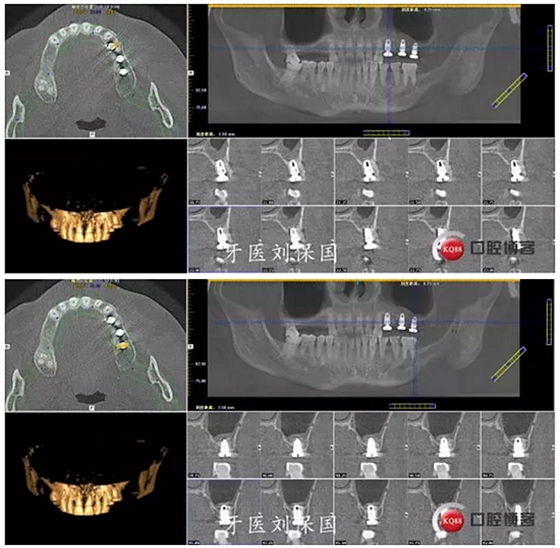

治療計(jì)劃及相關(guān)費(fèi)用已向患者講明,征得患者同意,口腔及頜面部常規(guī)消毒,鋪巾,5.1ml必蘭局部浸潤(rùn)麻醉下,切開,翻瓣,暴露牙槽骨,常規(guī)拔除患牙,清創(chuàng),沖洗,先鋒鉆定位,逐級(jí)擴(kuò)孔,在25,26位置行上頜竇內(nèi)提術(shù),植入bio-oss骨粉,在24,25,26位置分別植入Dentium 4.5*8mm植體各一枚,扭矩30Ncm,旋入愈合基臺(tái) 603R,縫合,沖洗。

3.術(shù)后CT: